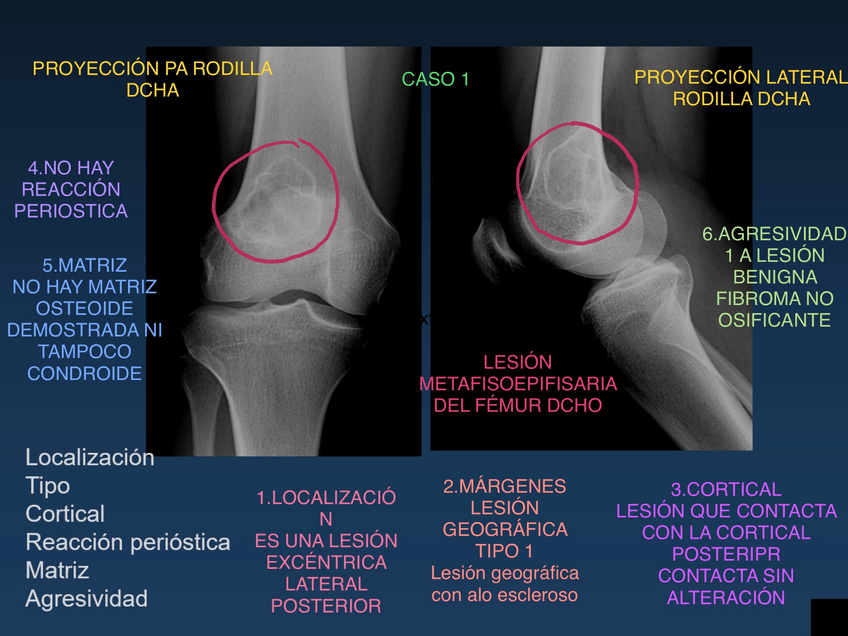

Ejemplos de RX, TC, RM de las enfermedades que hemos visto en clase o en prácticas. NO son fotos de clase ni de prácticas

BLOQUE-MUSCULO-ESQUELETICO.pdf